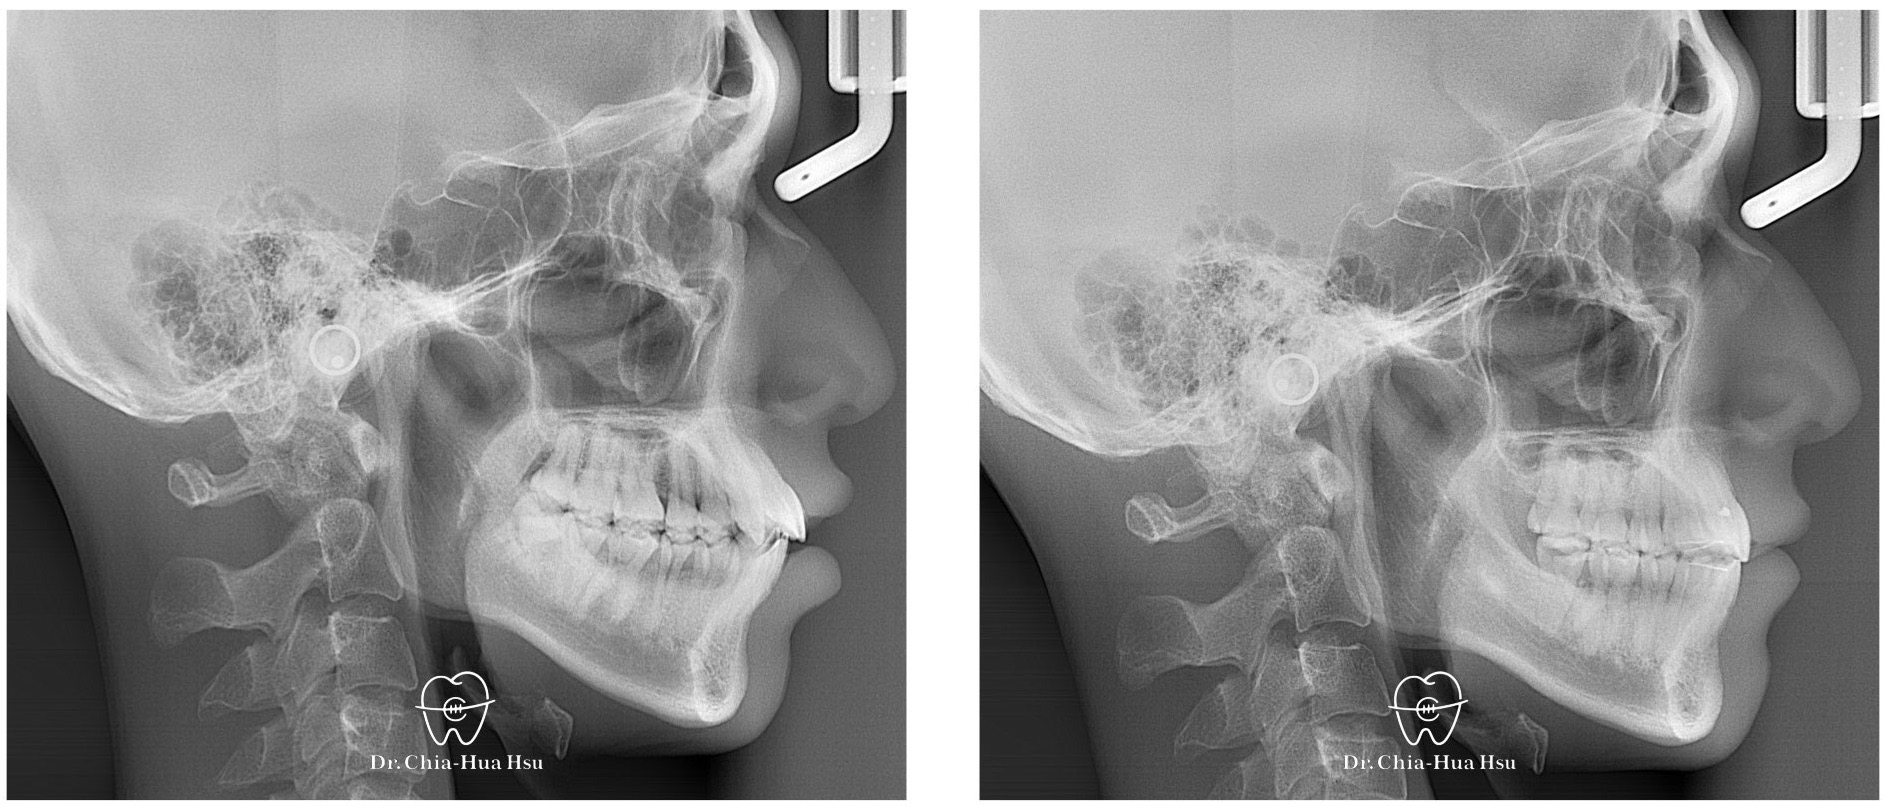

- 問題分析:患者是標準的骨骼一類咬合(Skeletal Class I)伴隨齒列擁擠以及嘴唇微凸。

- 治療方式:使用傳統金屬矯正器,拔除四顆小臼齒獲得空間,搭配二級橡皮筋牽引(Class II elastics)。

- 治療結果:齒列排齊,嘴凸也有顯著改善,甚至下巴輪廓更明顯。

治療前

治療後